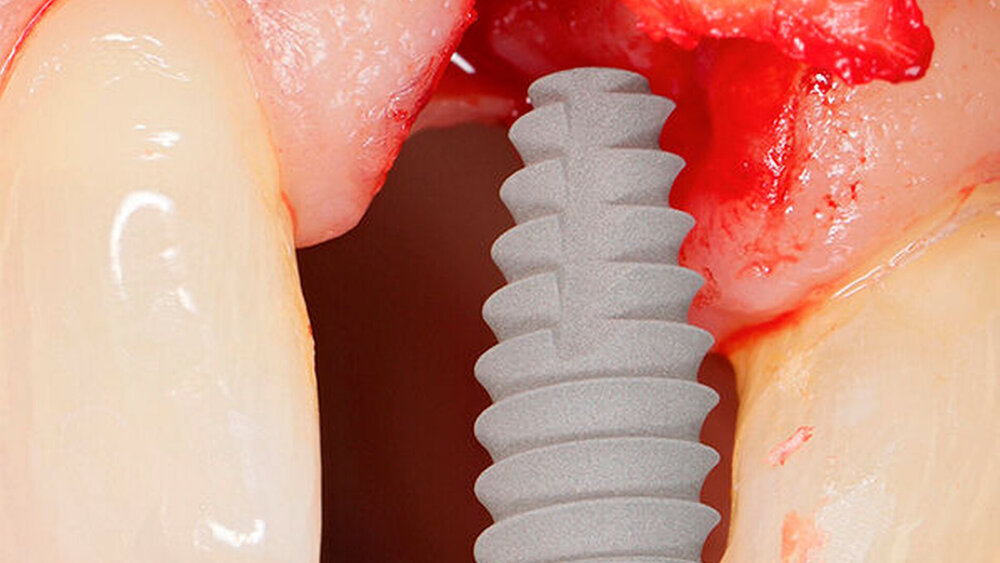

In welchen klinischen Anwendungen bietet das Implantat Vorteile?Hermann:Das neue CAMLOG PROGRESSIVE-LINE Implantat besticht durch sein innovatives parallel-konisches Makrodesign mit einem speziellen Gewinde, bei gleichzeitig bewährter Prothetikschnittstelle der Camlog-Linie. Dies bedeutet, dass in der chirurgischen Phase mit diesem Implantat eine zuverlässige Primärstabilität erzielt werden kann, speziell bei schwierigen anatomischen Voraussetzungen, wie z. B. bei der Sofortimplantation, bei reduzierter Kieferkammbreite oder konkav verlaufenden Alveoloarkämmen sowie bei weichem Knochen im Oberkiefer. Aufgrund des krestalen Verankerungsgewindes sehen wir zudem einen Vorteil bei der Platzierung des Implantats im Zusammenhang mit einer simultanen, offenen Sinusbodenelevation bei stark reduzierter Restknochenhöhe (2–3 mm). Auch einzeitige Verfahren lassen sich einfacher durchführen. Denn auch im kompromittierten Knochen erreicht das Implantat eine hohe vorhersagbare Primärstabilität.

Sind dann auch eher Sofortversorgungsprotkolle umzusetzen?Hermann:Die erzielte Primärstabilität ist in den meisten Fällen so hoch, dass eine sofortige provisorische Versorgung/Belastung möglich ist. Somit können wir unseren Patienten effiziente Behandlungsabläufe anbieten. Die Effizienz zeigt sich beispielsweise auch bei der Reduktion der Bohrschritte durch ein flexibles Bohrprotokoll. Gerade im weichen Knochen benötigen wir meist nur drei Bohrschritte bis zur Insertion des Implantats und erzielten eine exzellente Primärstabilität durch eine geringere Aufbereitung des Implantatbetts. Auf den zusätzlichen Einsatz nicht-ablativer Techniken (Osteotome) kann häufig verzichtet werden. Ein Teil der 80 von uns gesetzten PROGRES ‧ SIVE- ‧ LINE Implantate befindet sich bereits in der prothetischen Nachkontrolle. Das klinische und prothetische Outcome ist hervorragend. Es gibt weder chirurgische Komplikationen noch Probleme bei der Einheilung, und die prothetische Versorgung funktioniert perfekt.